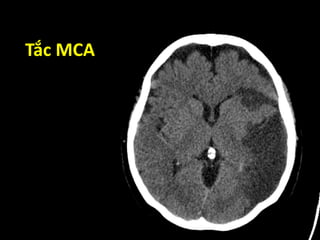

Vùng tưới máu

ACA MCA PCA

Nhìn trên Nhìn dưới

Tắc MCA

Các dấu hiệu sớm chẩn đoán

nhồi máu não trên CT Scan

• Dấu tăng tỉ trọng động mạch não

 “dot sign”

 “hyper dense” – dấu dây thừng

• Dấu hiệu gây ra bởi hiện tượng phù não

 Mất phân biệt xám-trắng

 Mất dải ruy-băng thùy đảo

 Xóa mờ nhân đậu

 Mờ rãnh Sylvius

 Mất các rãnh não

Dấu tăng tỉ trọng MCA

“dot sign”

“hyper dense”

Mất phân biệt xám – trắng